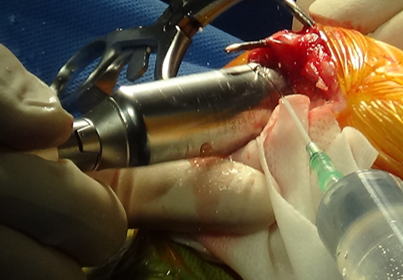

3) 수술 과정

수술 부위를 절개한 뒤, 정강이뼈 위쪽을 안전하게 노출한뒤 TPLO 전용 톱을 이용해 정강이뼈 위쪽을 원형으로 절골합니다.

.png)

수술 전 계획에서 계산한 값대로, 절골된 뼈 조각을 필요한 만큼 회전시켜 관절면 경사를 조정합니다.

회전한 뼈가 움직이지 않도록 TPLO plate와 screws로 단단하게 고정해 뼈가 안정적으로 붙을 수 있게 합니다.